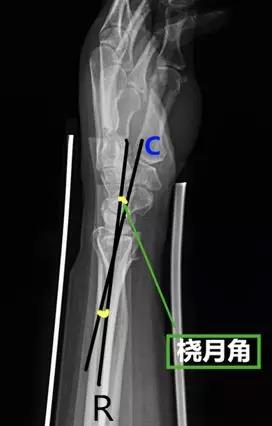

- 桡月角:在腕部侧位片上桡骨和月骨(近端与远端)中轴线的夹角。

- 正常值:0°~15°

- 临床意义:屈曲>15°提示掌曲不稳,背伸>10°提示背伸不稳。

- 头月角:腕部侧位片上头状骨和月骨中轴线的夹角。

- 临床意义:>20°提示腕关节不稳。

- 舟月角:在腕关节侧位片舟骨与月骨(近端与远端)中轴线的夹角。

- 正常值:30°~60°

- 临床意义:舟月角>70°提示腕背伸不稳,<30°提示腕掌屈曲不稳;>60°或移位>1mm,需要对舟骨进行切开复位内固定;舟月间距<3mm,间距>3mm提示舟月韧带撕裂。